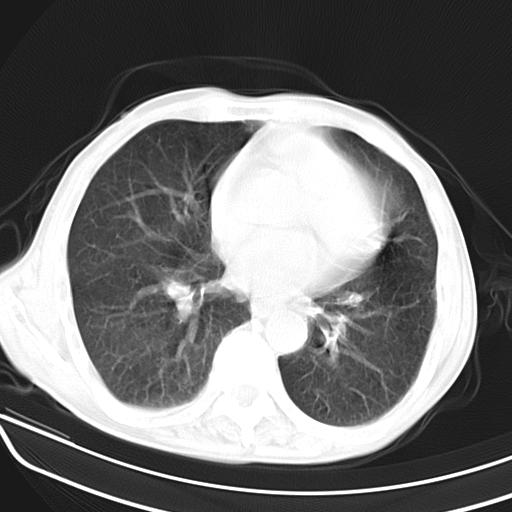

抗炎治疗10天后复查

抗炎治疗10天后复查:右上肺模糊阴影明显减少。